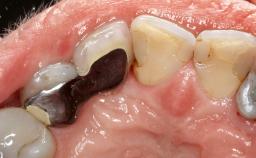

Peri-Implantitis Modified by the Presence of Submucosal Excess Cement: Reconstructive Therapy and a Ten-Year Follow-up

This case outlines the reconstructive therapy by Giovanni Salvi resulting in defect fill and inflammation-free peri-implant soft tissues at 10-year follow up. This case highlights the importance of regular monitoring of implants during supportive therapy.

A 30-year-old female patient was referred to the Department of Periodontology of the University of Bern, Switzerland, by a private dentist. Tooth 45 was congenitally missing and had been replaced with an implant three years prior to the first visit at the Department of Periodontology.